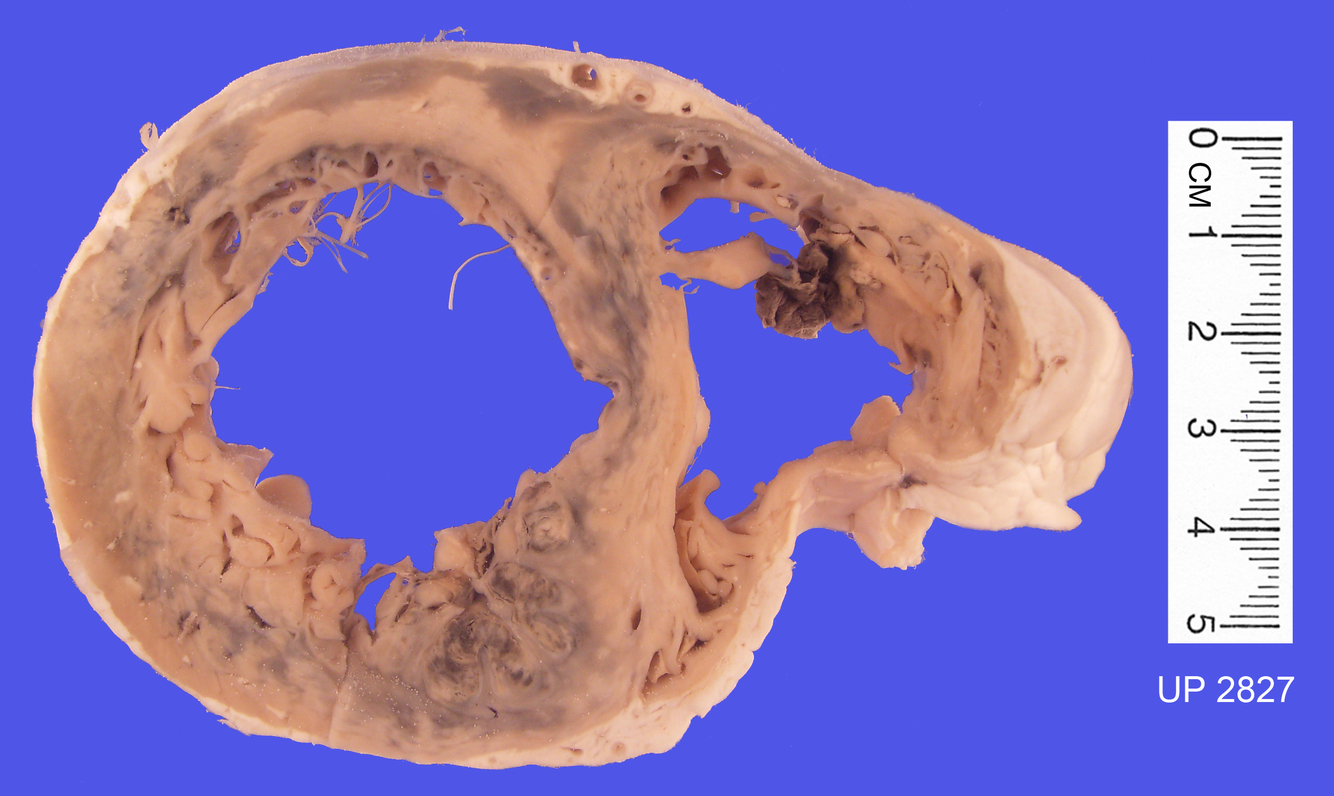

The specimen shows a large infarct of the myocardium involving the apex, the lateral and posterior walls of the left ventricle and much of the interventricular septum. This is the distribution of the left anterior descending coronary artery.

There is a pericarditis overlying the infarct and the infarct is seen as an irregular, transmural, yellow necrotic zone surrounded by a hyperaemic margin.

There is severe coronary artery stenosis as a result of atherosclerosis.